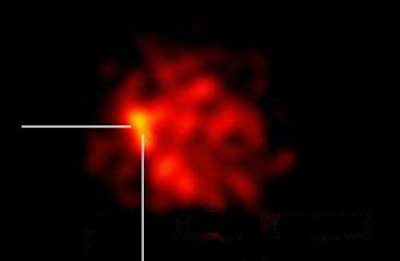

| Above, two sentinel lymph nodes are detected over the common iliac artery, right side. Histopathology showed that one contained micrometastatic deposits of urothelial bladder carcinoma. |

Overall, planar lymphoscintigraphy alone versus CT-enhanced lymphoscintigraphy detected two and 21 positive nodes, respectively, including 1/2 in patient 1, 0/6 in patient 2, 0/6 in patient 3, 0/4 in patient 4, 1/3 in patient 5, and 0/0 in patient 6, according to the results. Of these, only two positive nodes were detected by the blue dye marker, while the gamma probe detected 10 positive nodes peroperatively. Harvested nodes per patient ranged from six to 24, the total number of detected sentinel nodes per patient ranged from zero to six. All six patients were staged T2.

The results are very similar in the eight patients imaged since the poster was prepared, he said. "A lot of nodes were found in very aberrant localizations, with metastatic deposits where we didn’t expect to find them. And we find them exactly where the radiologist tells us they are."